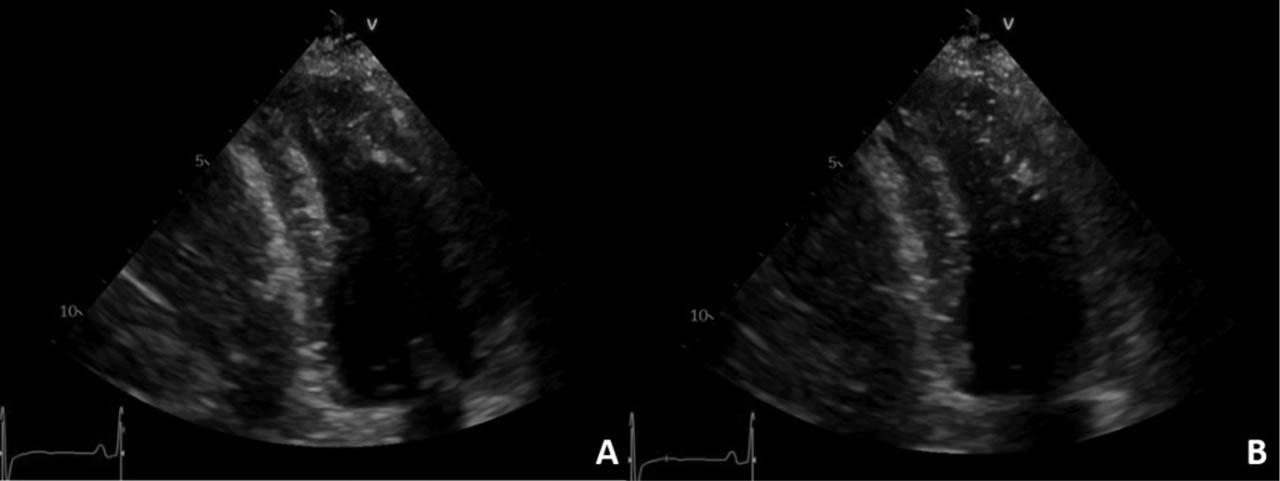

Figure 4

Transthoracic echocardiography, apical 2-chamber view, 2D examination: left ventricular apical hypertrophy in diastole (A) with systolic obstruction at this level (B).